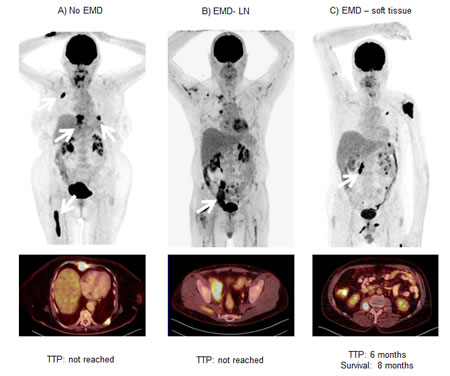

In 14/37 (38%) patients with extramedullary disease, TTP and OS was shorter than in the patients with no EMD (median TTP 3.2±3.4 m vs. 29.3±0.0 m, p=0.049; median OS 8.8±1.5 m vs. not reached, p=0.172; Figure 4A). However, sub-analysis of disease allocation revealed that presence of myeloma lesions in soft tissue structures (6/37, 16%) was associated with significantly shorter median TTP and median OS (Figure 4B). Subjects with soft tissue involvement turned out to have a median TTP of 1.4±0.5 months (vs. 10.2±5.2 m in all patients without soft tissue involvement; p=0.008) and a median OS of 4.7±3.3 months (vs. OS not reached; p=0.003). In comparison to patients with EMD and involvement of other organs, absence of soft tissue lesions was associated with an improved median TTP of 10.2±4.0 months (p=0.021) and median OS was not reached (p=0.013). Figure 5 shows an example of soft tissue involvement and limited survival of 8 months despite multidrug therapy including novel compounds. Interestingly, soft tissue involvement was associated with extensive intramedullary disease (>10 intramedullary lesions) in 5/6 (83%) patients. The remaining patient without intramedullary MM suffered from co-existing LN involvement, which occurred in the majority of EMD cases (11/14, 79%). On its own, presence of nodal involvement was associated with a slightly longer median TTP (6.6±3.2 m) and median OS 8.8±0.0 m as compared to EMD without LN involvement (median TTP 2.2±0.76 m, p=0.097; median OS 7.0±1.9 m, p=0.379).

Figure 5: Negative prognostic value of extramedullary soft tissue lesions. Display of three patients without (A) and with (B; C) extramedullary myeloma manifestations. Whereas patient A had exclusively intramedullary lesions, patients B and C presented with intramedullary and extramedullary disease. Patient B had mainly iliac lymph node involvement (arrow), patient C suffered from muscle manifestations (arrow). All patients received chemotherapy with novel agents after 18F-FDG-PET/CT; follow-up was 8 months in all. Whereas patients A and B have not progressed yet, patient C died 8 months after the PET scan. EMD = extramedullary disease, LN = lymph node, TTP = time to progression